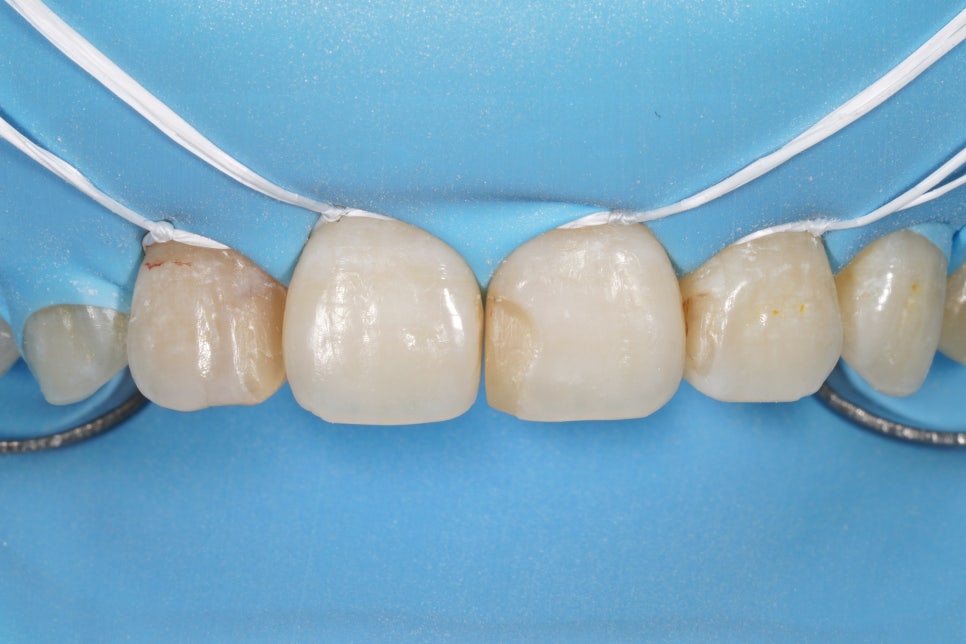

러버댐 사진

러버댐(ISODAM)을 걸고 나니

그냥 입안에서 봤을 때보다

기존 레진 치료한 부위가 확 티가 나죠?

이런 걸 입안에 붙이고 있었다니,

충격을 받으실 수도 있겠네요.

기존에 치료되어있던 레진은 다 갈아냅니다.